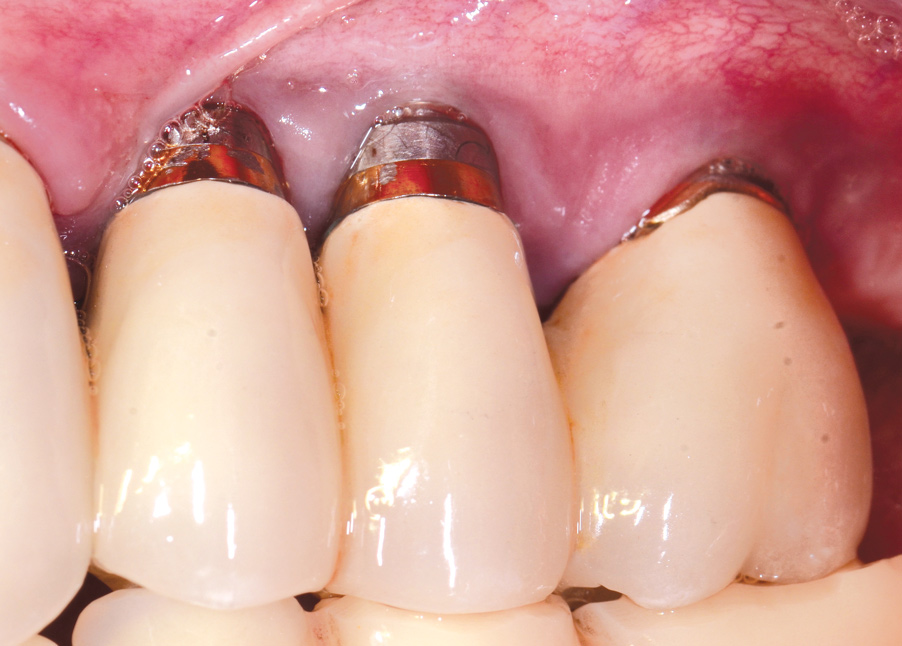

Dental implants have revolutionized the way in which clinicians treat and restore partially and fully edentulous patients and have demonstrated success for managing a broad range of clinical dilemmas. While implants have been highly predictable and have achieved long-term success, they are not immune from complications associated with improper treatment planning, poor surgical and prosthetic execution, material failure, and inadequate or infrequent maintenance. Among these problems are the biologic complications of peri-implant mucositis and peri-implantitis, which are inflammatory conditions in the soft and/or hard tissues surrounding dental implants (Figure 1 through Figure 4).1,2